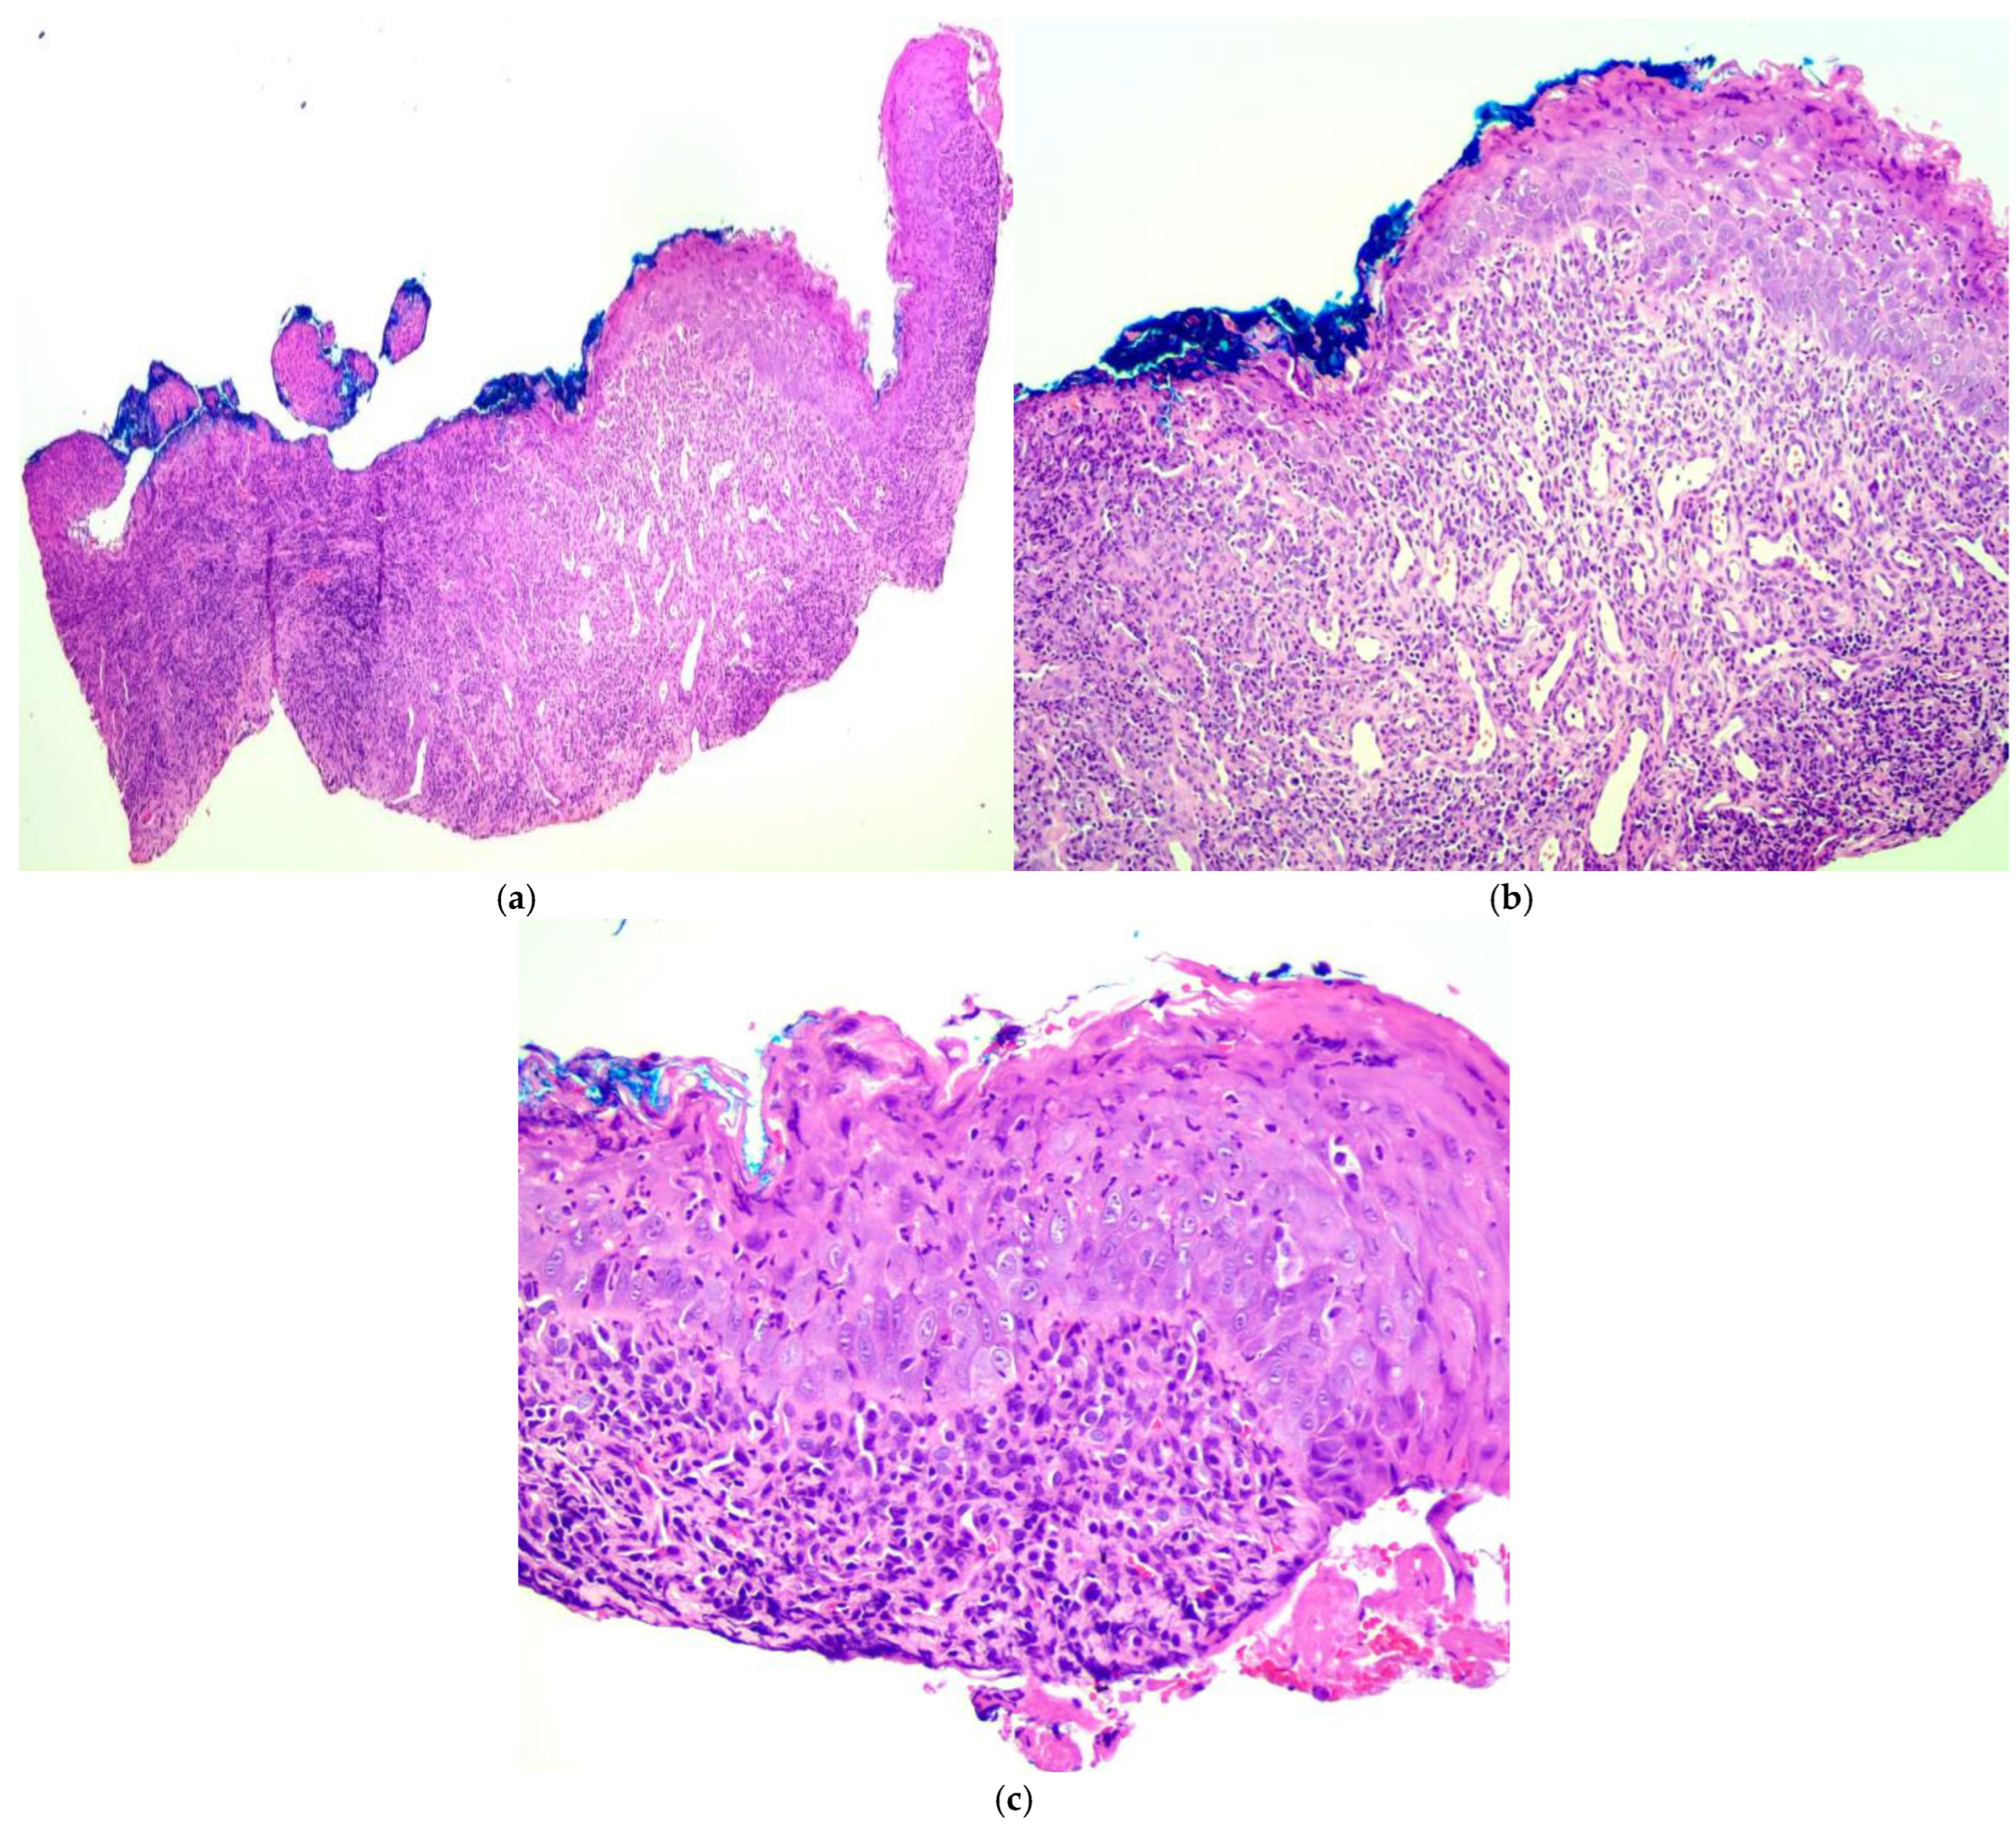

- Popa, C.; Sciuca, A.M.; Onofrei, B.A.; Toader, S.; Condurache Hritcu, O.M.; Botoc Colac, C.; Porumb Adrese, E.; Branisteanu, D.E.; Toader, M.P. Integrative approaches for the diagnosis and management of erosive oral lichen planus. Diagnostics 2024, 14, 692. [Google Scholar] [CrossRef] [PubMed]